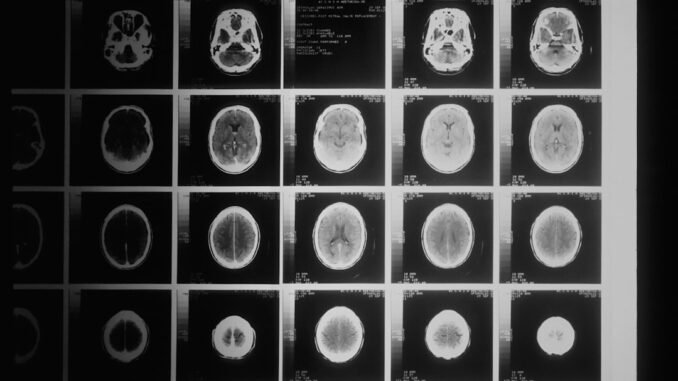

Traditionally, a neuroradiologist, often with years of specialized training, manually outlines these tumors slice by painstaking slice on MRI scans. It’s a labor-intensive, time-consuming process, and despite their expertise, there can be subtle variations between different observers, or even the same observer on different days. This inter-observer variability, small as it might seem, can have huge implications for treatment planning and, critically, for objectively assessing how a tumor responds to therapy in clinical trials. If you can’t accurately measure change, how can you truly know if a new drug is working? This is where automated, consistent segmentation steps in as a game-changer.

The challenge meticulously curated a dataset of multi-parametric MRI (mpMRI) scans. If you’re not familiar, mpMRI isn’t just one type of scan; it’s a suite of sequences, each providing distinct information. Think of it like different lenses on a camera, each revealing a different aspect of the subject. We’re talking T1-weighted images, T1-weighted images with contrast enhancement (T1ce), T2-weighted images, and Fluid-Attenuated Inversion Recovery (FLAIR) sequences. Each of these sequences highlights different tissue characteristics – water content, fat, blood flow, and the presence of contrast agents that help illuminate parts of the tumor where the blood-brain barrier is compromised. By integrating all this data, radiologists get a comprehensive picture, and more importantly, so do the sophisticated algorithms participating in BraTS-PEDs.